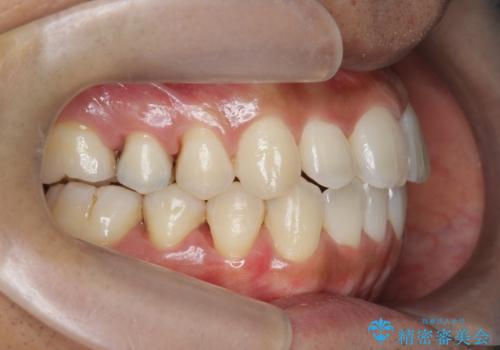

- 前歯のガタつきをきれいにしたい、と矯正治療を希望され来院されました。

マウスピース矯正インビザラインを用いてガタつきをきれいに並べていきます。

外側に傾斜していた前歯の角度も良くなり、「前歯の見た目が良くなった。」、と喜んでいただくことができました。